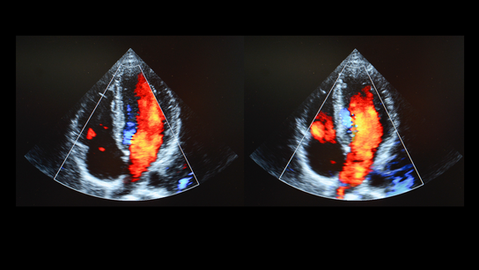

Cardiac Ultrasound Echocardiograms

What is an Echocardiogram? An echocardiogram or commonly referred to as “Echo,” is an ultrasound exam used to evaluate the heart and its movement in real-time.

These are no radiation-involved imaging studies and generally take 15-30 minutes to complete. Our qualified sonographers capture images of your heart and evaluate the chambers and valves, providing your doctor with the information they need to care for you.